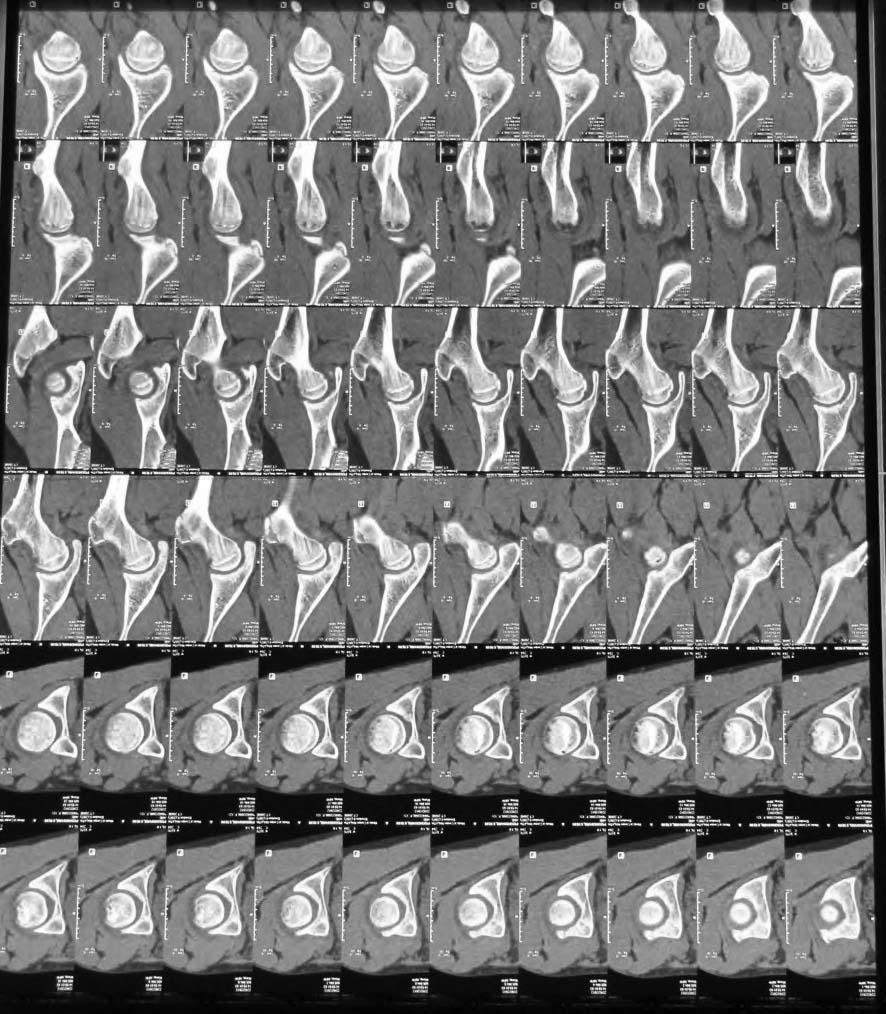

Аршак! Сделай КТ, лучше трехмерку. Дальше будем решать. Процесс по восстановлению эпифиза завершился, но с явной деформацией. АИФ

Классическая болезнь Легг-Кальве-Пертеса (ЛКП) проходить по пути: ишемия- асептический некроз головки- резорбция очага некроза-субхондральный перелом( проседание головки)- второй эпизод ишемии. В возрасте после 10 у девочек ( чаще активно занимающихся спортом) процесс, как правило начинается с "перегрузочного " субхондрального перелома. Лечение первый этап. Доступ: Бернский оперативный вывих бедра ( само рассечение капсулы,периоста по передней поверхности шейки произведет декомпрессию медиальной огибающей артерии, процедура: или trapdoore ( элевация хряща при его сохранности :J Pediatr Orthop. 1995 Jan-Feb;15(1):7-15."Trapdoor" procedure for osteonecrosis with segmental collapse of the femoral head in teenagers.) или остеохондральный дебридмент, резекция круглой связки.Обязательно: microfracturing, ревизия губы и ее подшивание. Второй этап через 3-4 мес в зависимости от сохранности головки или задняя ротационная остеотомия по Соколовскому ( передняя опасна из-за натяжения медиальной огибающей артерии) или вальгизирующая ( овал головки расположить горизонтально). С уважением Филипчук.

In this age prognosis is bad , but I think that she will improve after Vagus osteotomy -the goal is to remove necrotic part of the head from the weight bearing edge of the acetabulum

Отправитель: Arshak Mirzoyan 25 Сентябрь 2012, 22:35

I’ve sent patient to doctor who has superior experience of hip arthroscopy. If head’s “working surface” will be found we’ll think about hip reconstruction. I’ll keep you informed, thanks for your concerns of this case and to all who replied

I was just wondering if my vision of the problem was correct and if you refered the child for hip scope it means we were looking at the same direction:-))